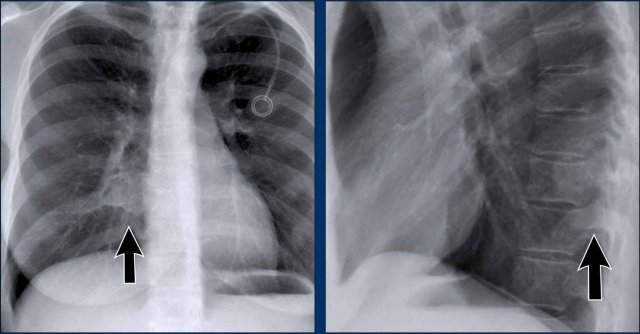

Hidden Areas (3): Pneumonia Below the Diaphragm

In this case, a pneumonia was primarily located below the right diaphragmatic dome (yellow arrow), within the posterior basal segment of the right lower lobe.

• On the lateral view, there is an increase in opacity over the lower thoracic vertebrae, indicating lower lobe consolidation (arrow).

• Again, image magnification may be necessary for adequate assessment.